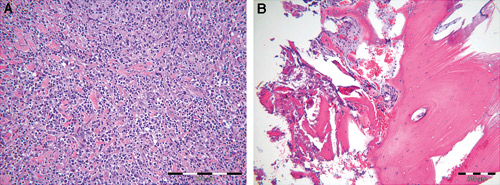

Det ble utført en insisjonsbiopsi fra regio 14–15, både i slimhinne og i bein, som viste nekrotisk benvev, men uten at dette ga klare holdepunkter med tanke på endelig diagnose (Figur 4 A og B). Problemene til pasienten ble tatt opp til tverrfaglig diskusjon, hvor en på grunnlag av forløpet konkluderte med at pasientens problemer mest sannsynlig skyldtes symptomer som var forenlig med en HZ infeksjon. Fordi pasienten kun var sporadisk til poliklinisk observasjon var det ikke mulig å stille diagnose basert på vesikkeldannelser. Blodprøver har i tillegg begrenset verdi, da antistoff mot VZV er svært vanlig i befolkningen. Det tok totalt fem måneder før pasientens symptomer avtok. Pasienten var sykemeldt i hele perioden, med redusert fødeinntak på grunn av kjevesmerter som gav et totalt vekttap på ca. 12 kg. Foreløpig er kun 12 og 13 behandlet endodontisk. Resten av tennene i 1. kvadrant er under observasjon med tanke på eventuelle endodontiske senkomplikasjoner. Pasienten er nå smertefri, men har fortsatt noe ubehag ved påbiting på 12 og 13.

Figur 4 A og B. Histopatologisk snittbilde fra både slimhinne (A) og bein (B). Prøven fra slimhinnen viser inflammert vev med betennelsesceller, mens prøven fra alveolarprosessen viser normal beinstruktur og områder med nekrotisk vev.

Serologisk test er en annen metode for å detektere VZV antistoff i serum (IgM antistoff). Antistoffpåvisning er imidlertid ingen indikasjon for sykdom, da dette vil finnes hos alle som har vært utsatt for smitte. Reaktivert HZ-infeksjon gir bare unntaksvis titerstigning (13). Metoden er derfor uegnet i denne sammenheng. Vår diagnose er derfor basert på sykdomsutvikling og ikke bekreftet av laboratoriefunn. Intraorale utbrudd av HZ vil kunne forekomme i alle områder i munnslimhinnen og er karakterisert ved kraftig enantem. Tilstanden kan likne på akutt herpetisk stomatitt, men opptrer nesten alltid unilateralt og avgrenset. Prodromal smerte kan mistolkes som tannpine når orale vev rammes. Det er derfor viktig med grundig anamnese og klinisk utredning (14). Ved intraoralt utbrudd av HZV er det i flere rapporter nevnt at sykdommen kan være dramatisk med sterke smerter, osteomyelitt og nekrose i underliggende bein, i noen tilfeller med påfølgende avstøting av flere tenner (7,10). Dette kan forklare funnet av nekrotisk vev i vår biopsi og at sensibiliteten i samtlige tenner i kjevehalvdelen var negativ. Infeksjon i tennene 12 og 13 må i denne sammenheng tolkes som en sekundær infeksjon på grunn av kompromittering av pulpa. Bortfall av vitalitet i øvrige tenner kan på sikt også tenkes å gi sekundærinfeksjoner, med påfølgende behov for endodontisk terapi. For pasienten vil sykdommen derfor også kunne få store økonomiske følger. Siden denne varianten av HZ er relativt sjelden, kan den være vanskelig å definere inn i trygdereglene.